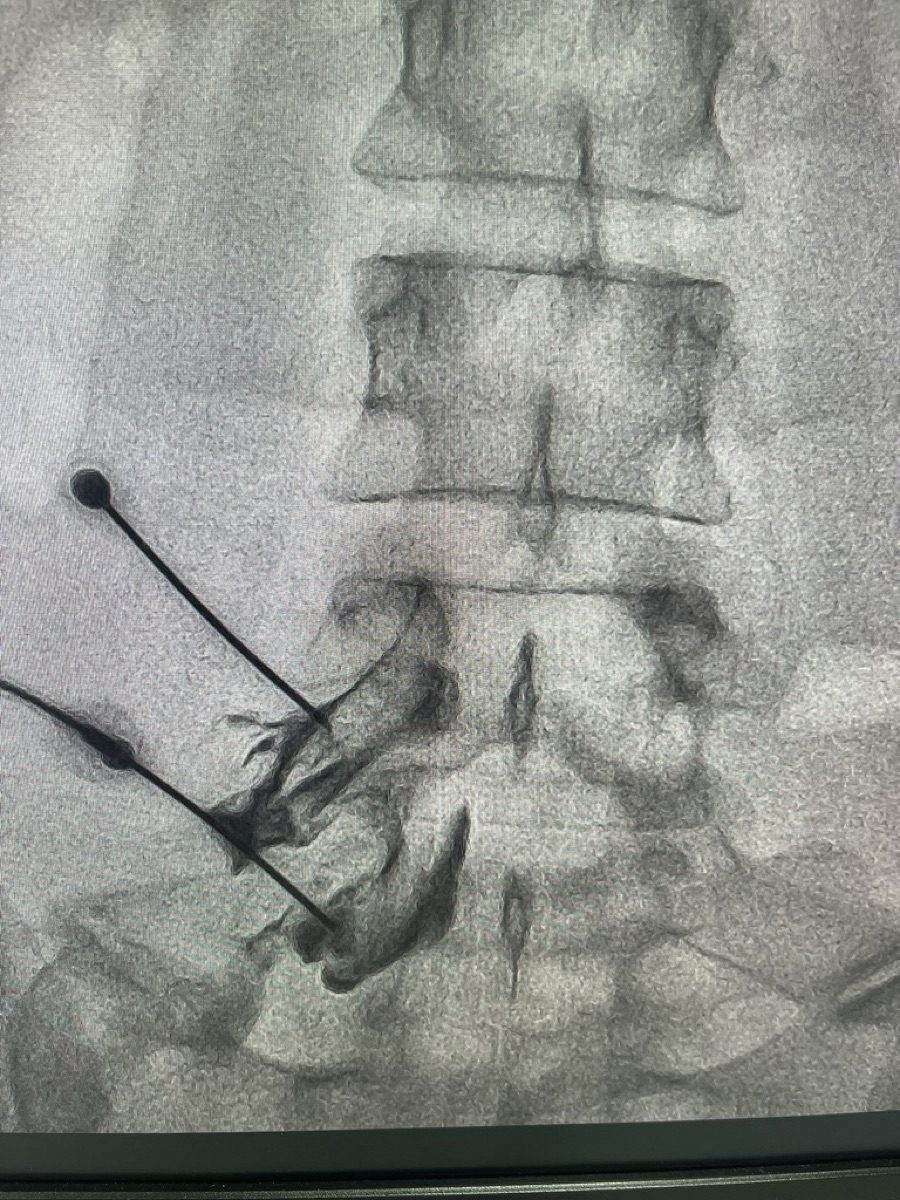

How is an epidural steroid injection performed?

You lie face-down on a padded table. The skin is first numbed with local anaesthetic. Under live X-ray (fluoroscopy) guidance, a thin needle is guided to the exact spot in the epidural space. The steroid is then injected with precision. The whole procedure takes about 15–20 minutes.